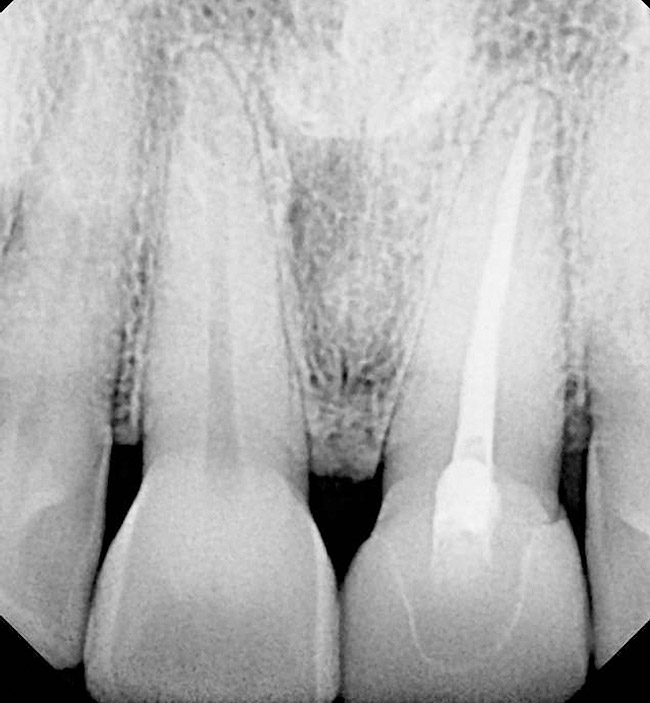

A 54-year-old woman was referred for treatment of a fractured maxillary right lateral incisor, secondary to recurrent subgingival decay. Clinical and radiographic examination revealed a high smile line; a thin, highly scalloped biotype; class II deep bite; a thin labial plate (< 2mm) with 4 mm of vertical bone loss; and class I interproximal height of bone24 (Figure 9 and Figure 10).

Figure 10  Periapical radiograph of the maxillary right lateral incisor with root fracture.

Figure 10